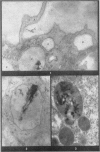

A series of experiments was undertaken to test the action of polyvinyl pyridine-N-oxide (P204) on the cytopathic effects of chrysotile asbestos dust in experimental animals. Organ culture studies were undertaken using pieces of guinea-pig lung, and in addition to this the lesions produced by the intrapleural injection of chrysotile were studied after treatment with varying doses of P204. The results from both series of experiments were unfortunately negative and P204 appeared unable to modify asbestos lesions in any way. These findings contrast sharply with the marked ability of P204 to protect tissues from the effects of silica dust. It is suggested that these differences are due to the fact that while silica is rapidly toxic to macrophages, asbestos is not and many healthy macrophages and giant cells can be found in asbestos lesions packed with dust several weeks after injection. The fibrous tissue that is eventually produced in response to asbestos dust is probably produced by a slower and more insidious process than that stimulated by silica, and this process is not modified by the presence of P204.